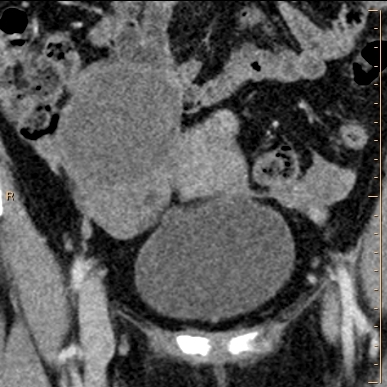

Conventional coronal CT through pelvis shows right ovarian cyst, otherwise unrerkanle

Virtual non-contrast image shows ovarian parenchyma below cyst is somewhat hyperdense

Iodine map shows no uptake in parenchyma below right ovarian cyst. Spectral curves confirm suspicion: magenta curve (ROI in left ovary) shows rise on low keV, consistent with iodine uptake. Blue curve (ROI in right ovarian parenchyma) remains flat, …

Iodine map shows no uptake in parenchyma below right ovarian cyst. Spectral curves confirm suspicion: magenta curve (ROI in left ovary) shows rise on low keV, consistent with iodine uptake. Blue curve (ROI in right ovarian parenchyma) remains flat, and actually decreases a bit on lower keV, consistent with lack of iodine.

Iodine overlay image shows absent iodine uptake.